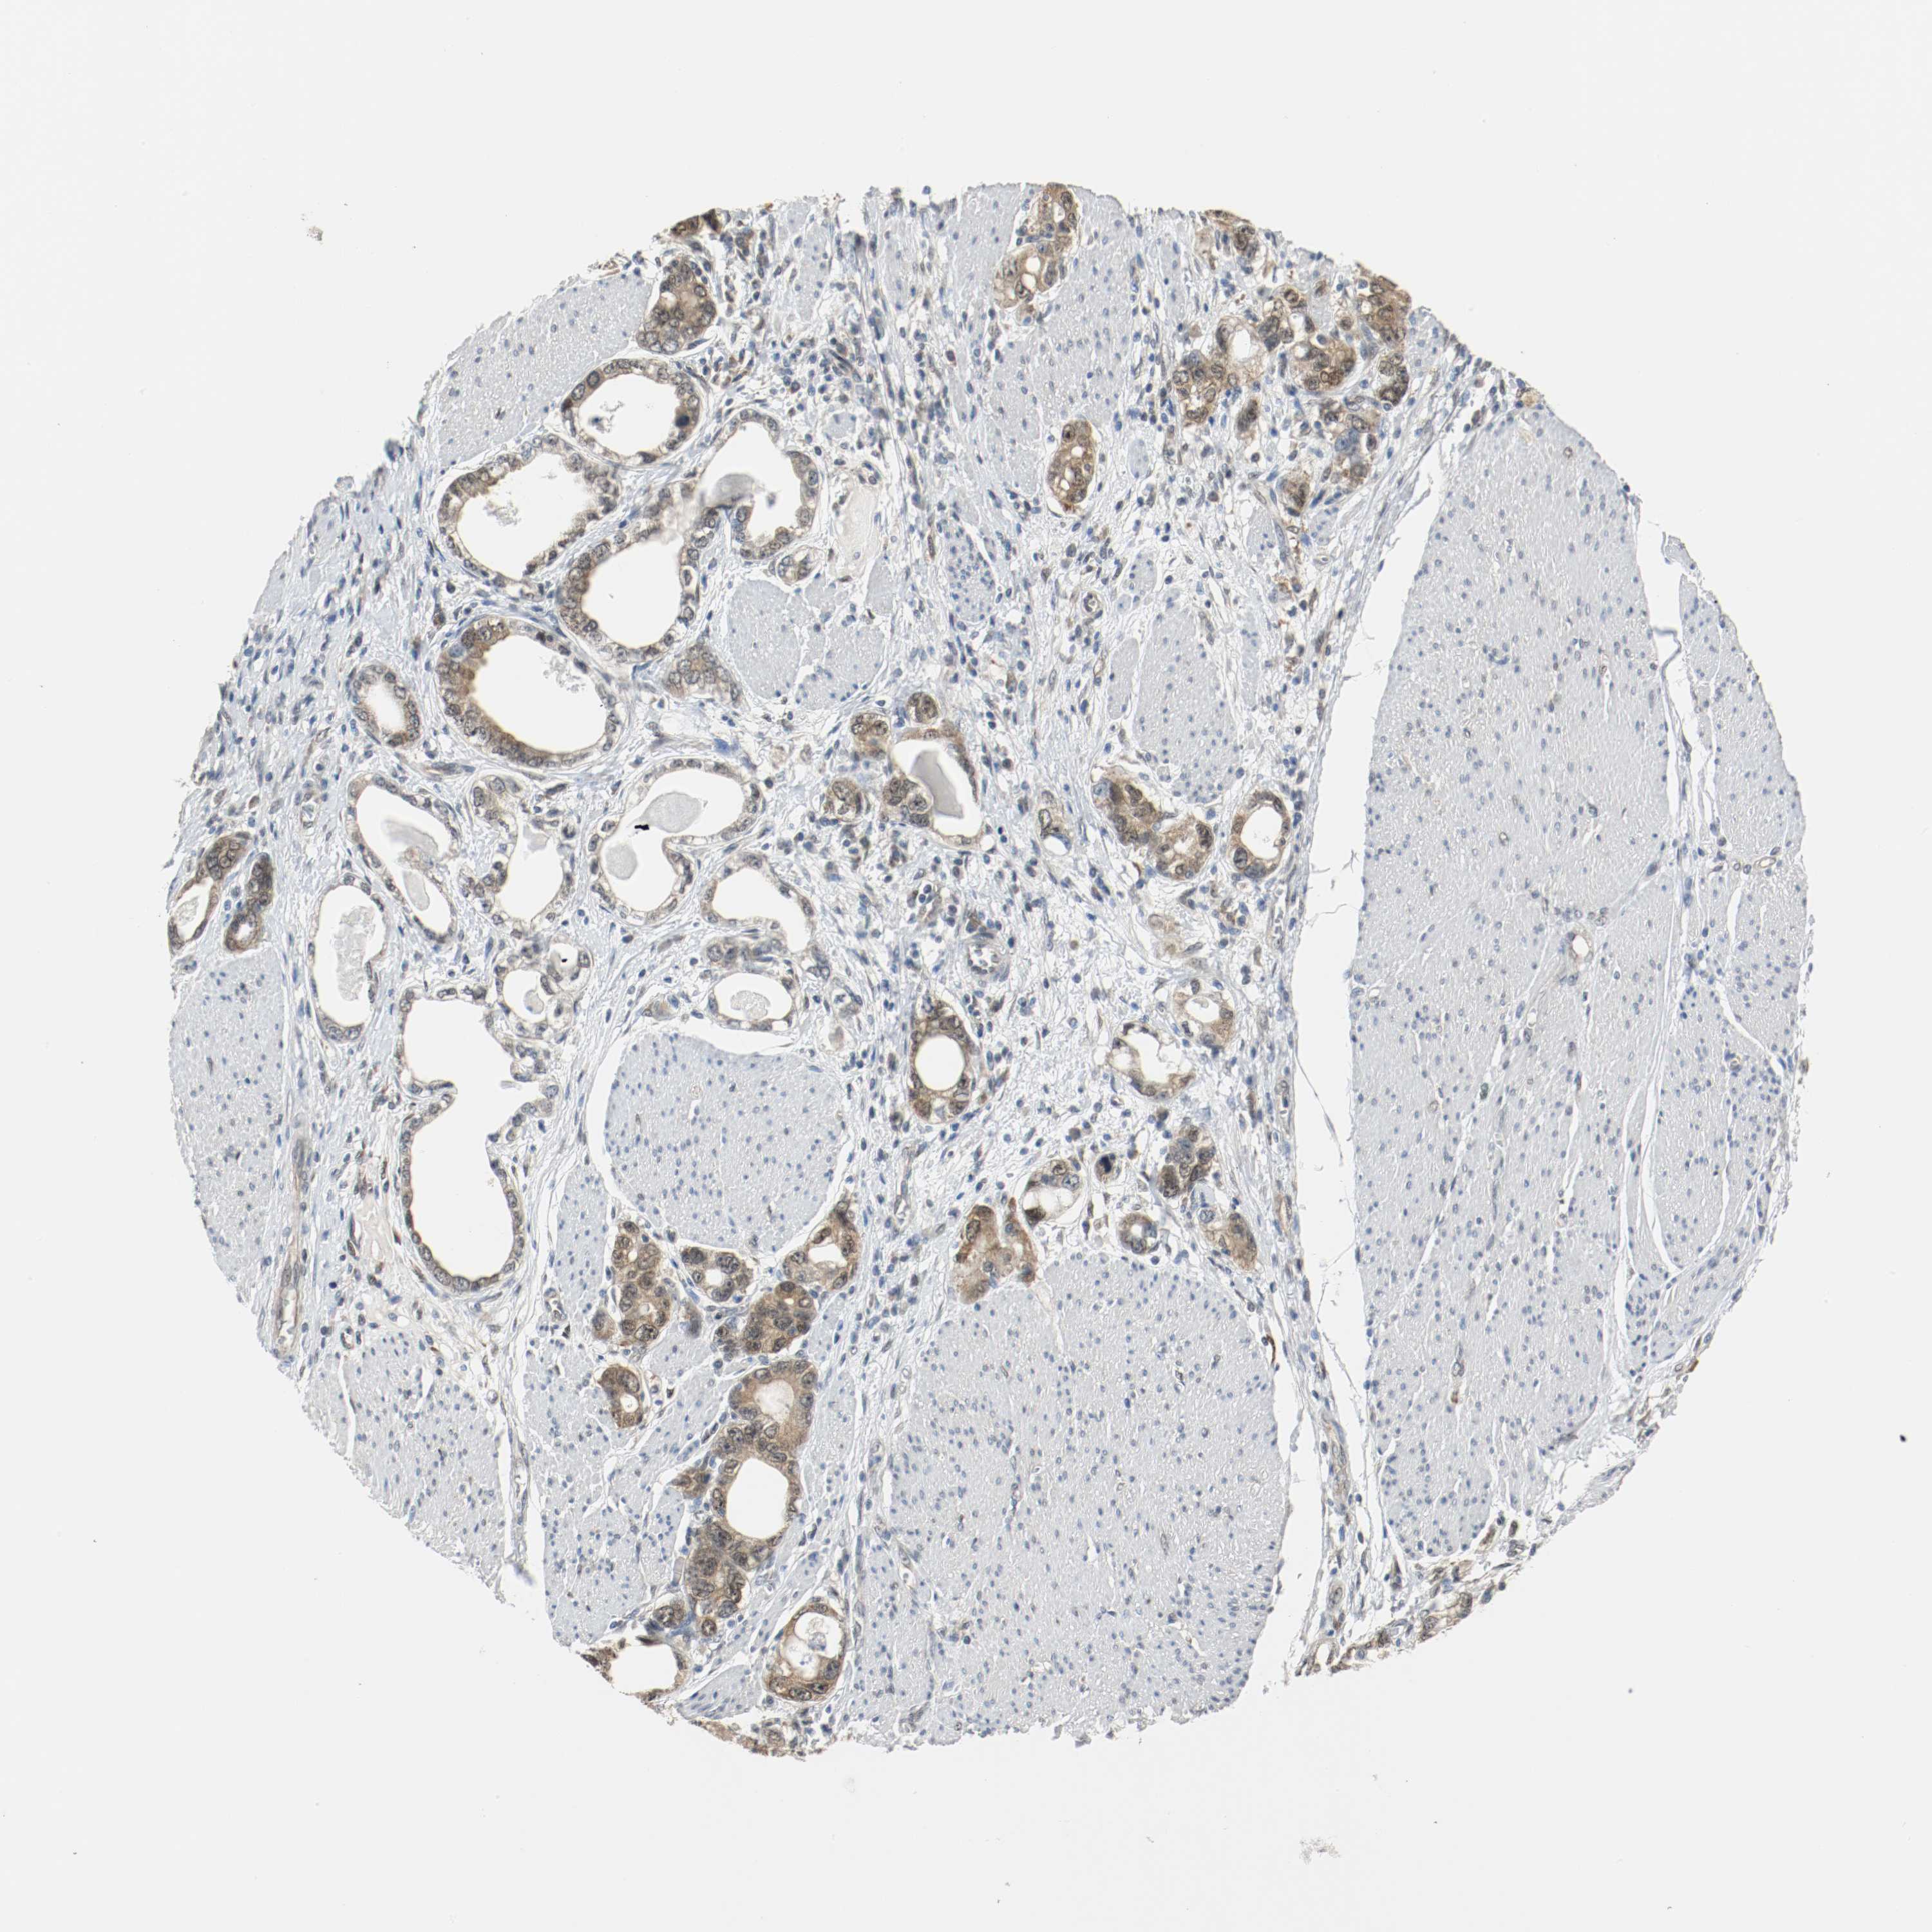

STOMACH CANCER - Protein expressioni

A mouse-over function shows sample information and annotation data. Click on an image to view it in a full screen mode. Samples can be filtered based on level of antibody staining by selecting one or several of the following categories: high, medium, low and not detected. The assay and annotation is described here.

Note that samples used for immunohistochemistry by the Human Protein Atlas do not correspond to samples in the TCGA dataset.

Antibody stainingi

Antibody staining in the annotated cell types in the current human tissue is reported as not detected, low, medium, or high, based on conventional immunohistochemistry profiling in selected tissues. This score is based on the combination of the staining intensity and fraction of stained cells.

Each image is clickable and will lead to virtual microscopy that enables deeper exploration of all samples and also displays staining intensity scores, fraction scores and subcellular localization as well as patient and tissue information for each sample.

Antibody HPA043900

Antibody CAB004541

Staining

High

Medium

Low

Not detected

Intensity

Strong

Moderate

Weak

Negative

Quantity

>75%

75%-25%

<25%

None

Location

Nuclear

Cytoplasmic/membranous

Cytoplasmic/membranous,nuclear

Adenocarcinoma, NOS

Adenocarcinoma, High grade